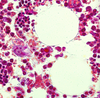

granulocytic cell nest (bone marrow)

Erythroid cell nests (bone marrow)

the white blobs

adipocytes (bone marrow)